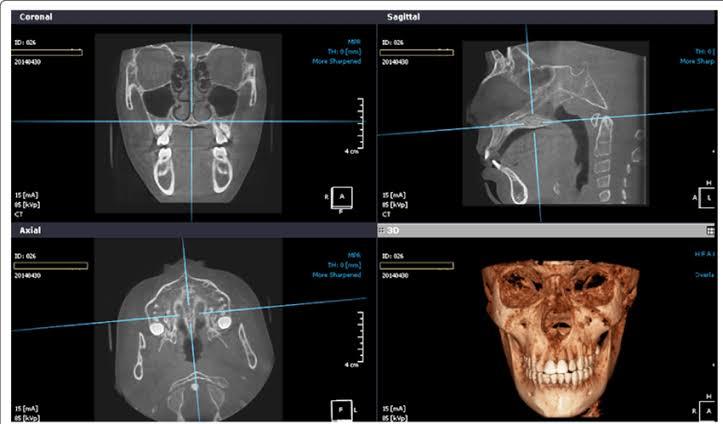

CBCT Imaging